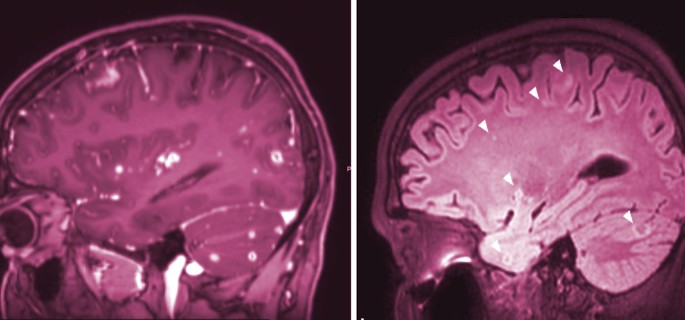

Zur Diagnose gehören normalerweise eine körperliche Untersuchung, eine Lumbalpunktion zur Entnahme von Liquor (Rückenmarksflüssigkeit) zur Analyse, bildgebende Verfahren wie CT- oder MRT-Scans des Gehirns und Labortests wie Blutuntersuchungen.

Die Behandlung der miliartuberkulösen und tuberkulösen Meningitis erfordert eine frühzeitige medizinische Intervention und eine umfassende Therapie. Es werden in der Regel mehrere Antibiotika gleichzeitig verabreicht, um die Tuberkulose-Bakterien effektiv zu bekämpfen und die Entzündung zu reduzieren. Die Behandlung dauert in der Regel mehrere Monate oder sogar Jahre, abhängig von der Schwere der Erkrankung und dem Ansprechen des individuellen Patienten auf die Medikamente.